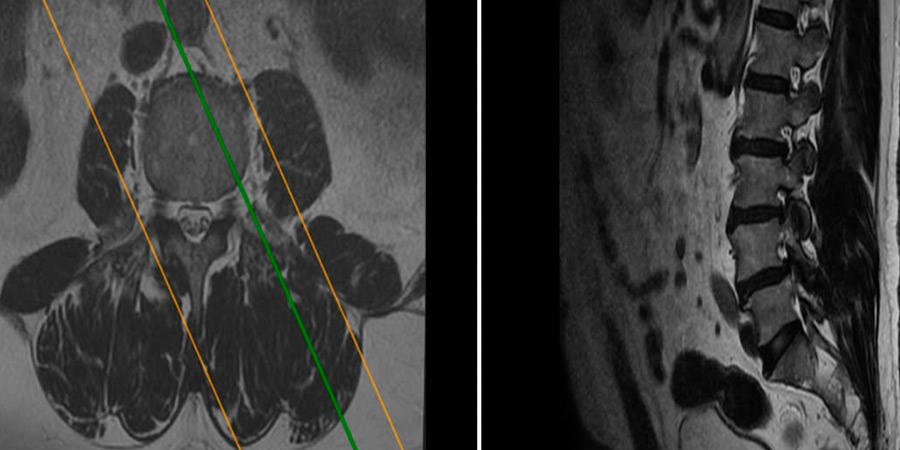

Para determinar la existencia de tumores o de cualquier otra enfermedad que pueda desarrollarse, el médico solicitará pruebas diagnósticas por imagen como una resonancia magnética o una tomografía computarizada. Estos estudios permiten visualizar la localización exacta del tumor y evaluar su tamaño y características.